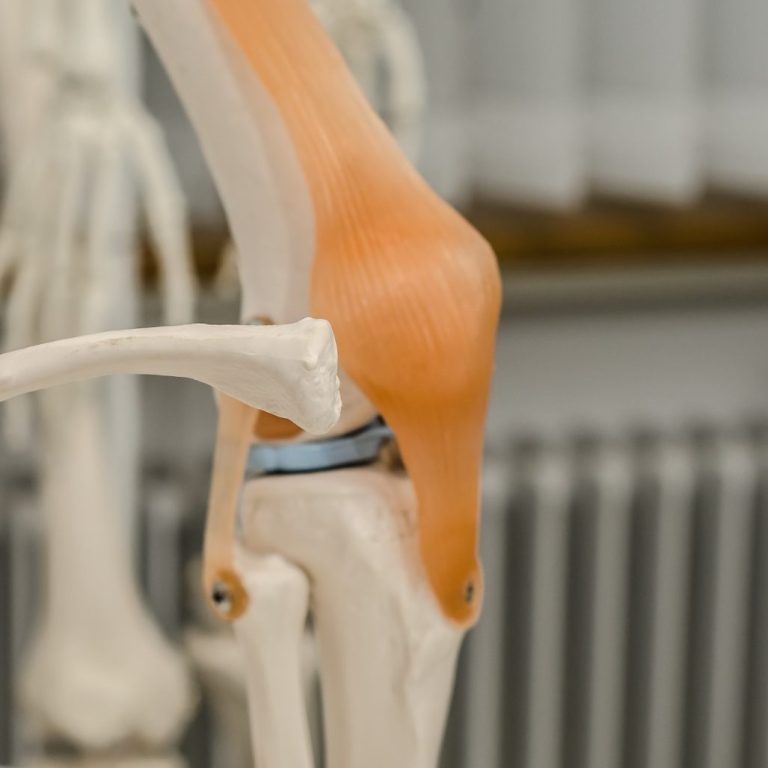

Arthroskopie

mit Millimetergroßen Instrumenten können viele Operationen an Gelenken minimal invasiv durchgeführt werden

Knie

Operation

häufig ist nicht nur das Kreuzband, sondern auch weitere Gelenkanteile geschädigt. Wir kümmern uns um alles...